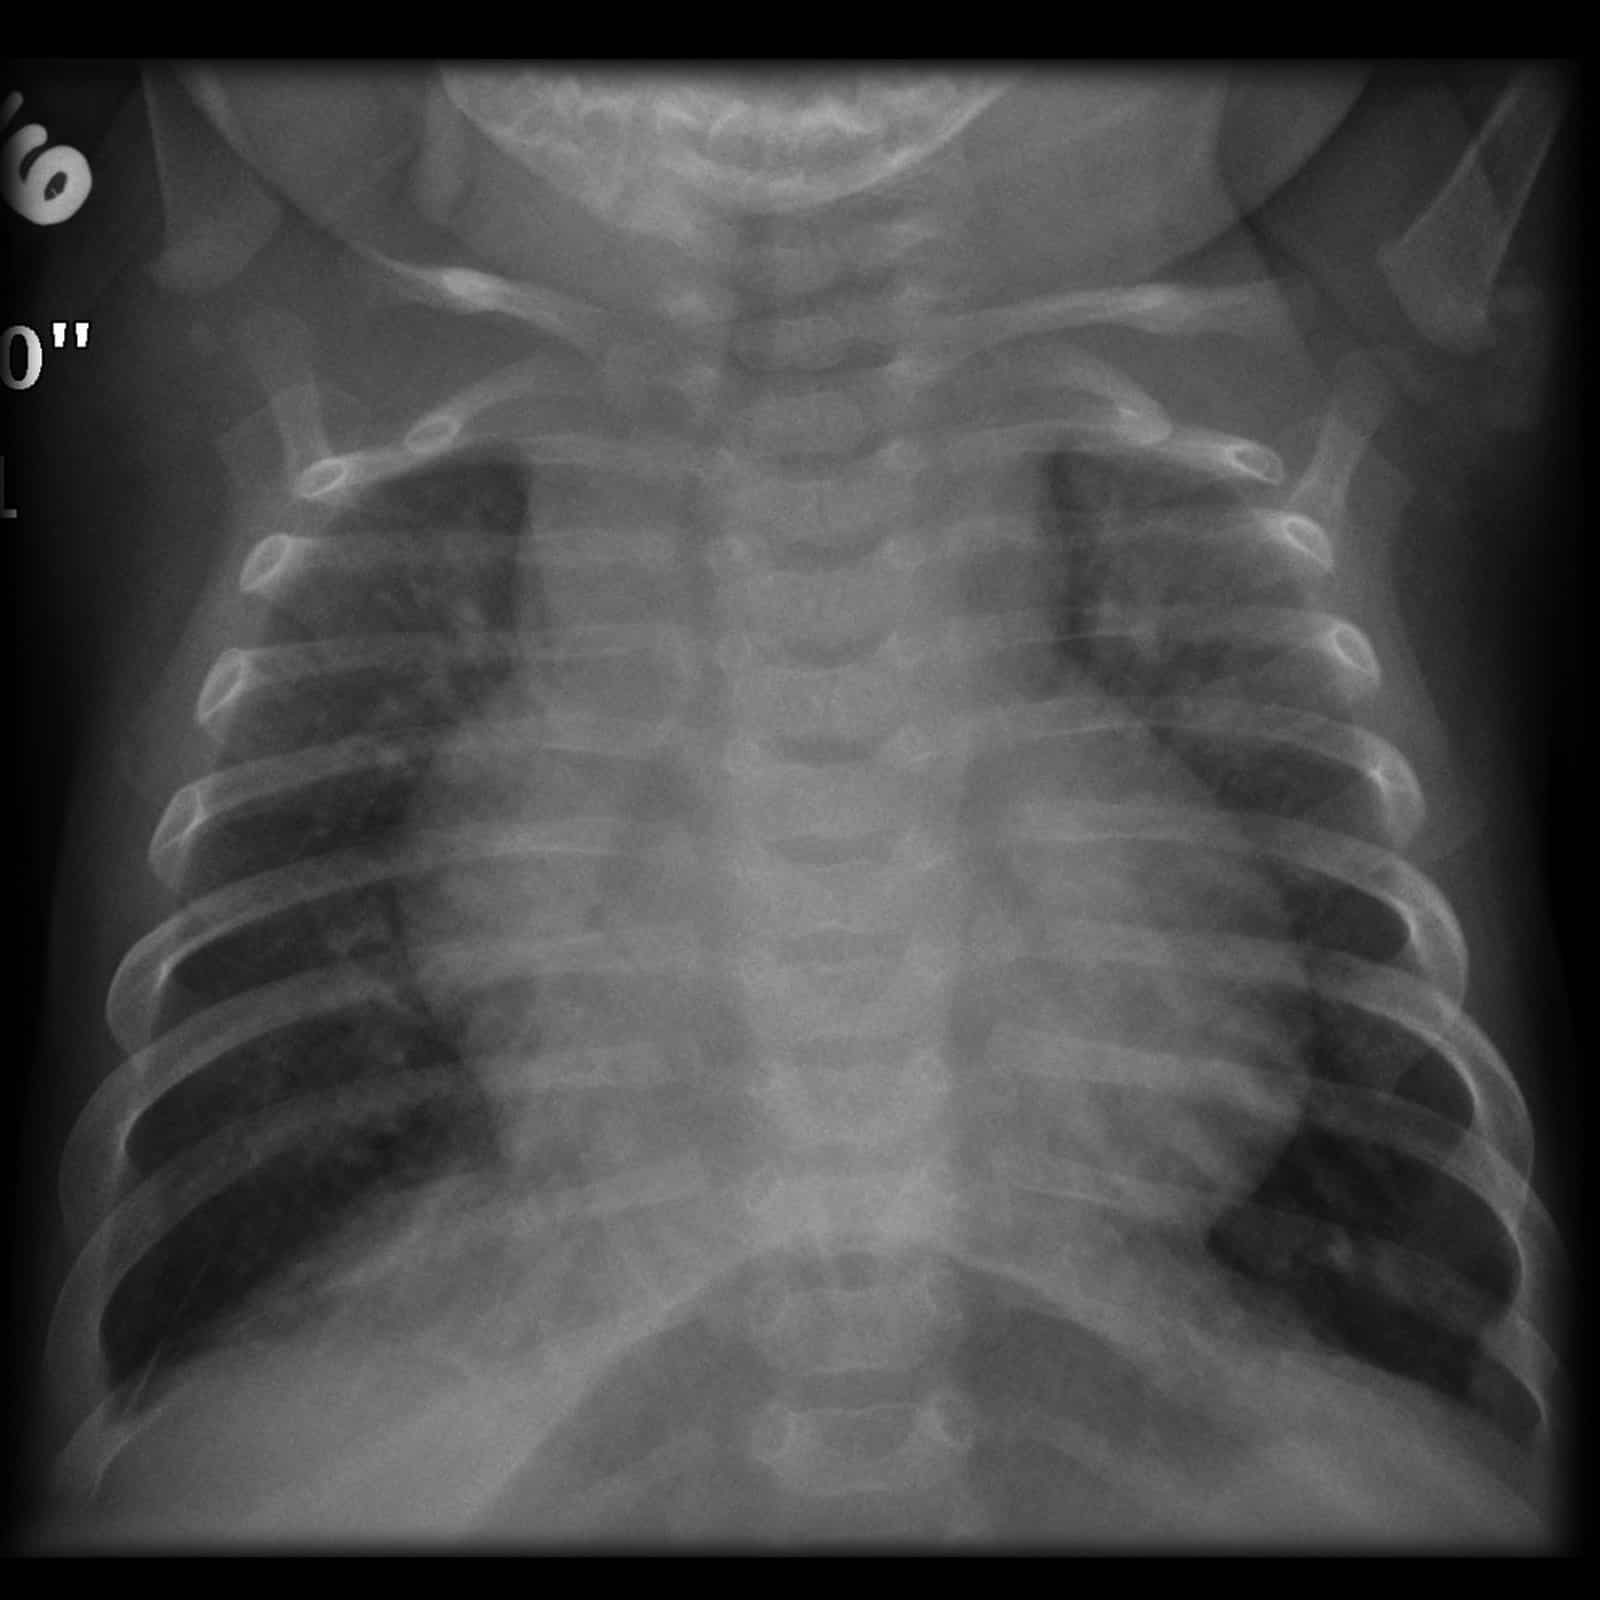

Ventricular septal defect (VSD) Cardiomegaly with plethoric lungs and What Is A Plethoric Lung Fields Web although absolute lung volumes can be measured by either gas dilution techniques or body plethysmography, the former. Web thoracic segmentations include lung parenchyma, primary tumor, atelectasis, adhesions, effusion, and other. Web plethoric lung fields should raise suspicion of pulmonary venous hypertension or a systemic to pulmonary. What Is A Plethoric Lung Fields.

Portable chest Xray showing cardiomegaly and bilateral plethoric lung What Is A Plethoric Lung Fields Web thoracic segmentations include lung parenchyma, primary tumor, atelectasis, adhesions, effusion, and other. Web although absolute lung volumes can be measured by either gas dilution techniques or body plethysmography, the former. Web plethoric lung fields should raise suspicion of pulmonary venous hypertension or a systemic to pulmonary. What Is A Plethoric Lung Fields.

Chest Xray showing cardiomegaly with hyper inflated lung fields and

Chest Xray showing cardiomegaly with hyper inflated lung fields and What Is A Plethoric Lung Fields Web thoracic segmentations include lung parenchyma, primary tumor, atelectasis, adhesions, effusion, and other. Web plethoric lung fields should raise suspicion of pulmonary venous hypertension or a systemic to pulmonary. Web although absolute lung volumes can be measured by either gas dilution techniques or body plethysmography, the former. What Is A Plethoric Lung Fields.